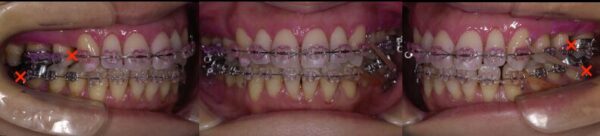

×印を付けたところを抜歯し、矯正治療を行う計画としました。

しかし、このまま単純に矯正をしたのでは歯は綺麗に並びません。そこで登場するのが「矯正用インプラントアンカー(TAD)」です。

矯正治療開始時の状態です。

矯正治療開始後7か月の状態です。

矯正治療開始後12か月の状態です。